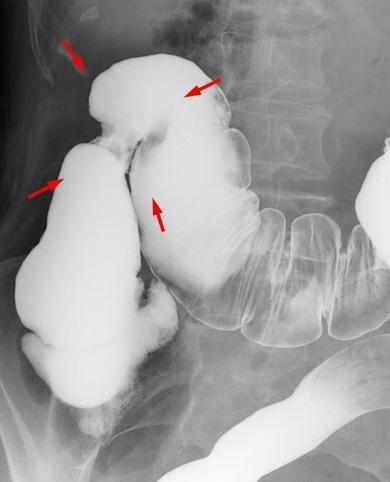

A case of tuberculosis of the ascending colon that endoscopically showed an 0-IIc type early cancer-like appearance in the initial examination.

Inflammatory or ulcerative disease / lesions/tuberculosis

Large intestine(Colon)/Ascending colon

X-ray

40 -